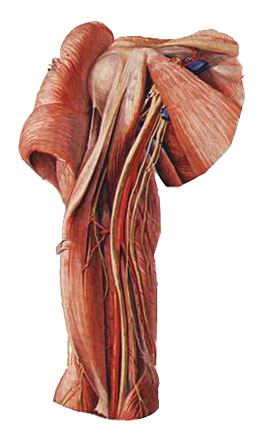

(2)股神经 (2) the femoral nerve

经腹股沟韧带深面,股动脉外侧进入股三角,肌支支配股肌前群,皮支支配股前部皮肤。 After lateral femoral artery deep to the inguinal ligament into the femoral triangle, before vastus muscle branch dominated group, femoral cutaneous branches dominate the skin. 股神经皮支有一长支,伴大隐静脉下降至足内缘,称隐神经。 Cutaneous branch of the femoral nerve with a long branch, with the great saphenous vein down to within a foot edge, called the saphenous nerve. 股神经损伤,股肌前群瘫痪,膝跳反射消失。 Femoral nerve damage, paralysis before the vastus group, the knee-jerk reflex.

(3)闭孔神经 (3) the obturator nerve

穿闭孔,伴闭孔动脉走行,支配股内侧肌,闭孔神经损伤,患腿不能伸到健腿上。 Wear closed-cell, with obturator artery course, dominate the medial femoral muscle, obturator nerve injury, suffering from leg extends not healthy legs.

(3)坐骨神经 (3) the sciatic nerve

坐骨神经是全身最大的神经。 Sciatic nerve is the largest body. 于梨状肌下缘出骨盆,行于臀大肌深面,经坐骨结节与大转子连线的中点,下行至腘窝,分为胫神经和腓总神经。 At the lower edge of the pelvis piriformis, the line in the deep surface of the gluteus maximus, the midpoint of the greater trochanter and the ischial tuberosity through wiring, down to the popliteal fossa, into the tibial nerve and the common peroneal nerve. 坐骨神经本干布于髋关节和股肌后群。 The sciatic nerve with a dry cloth in the hip and thigh muscles after the group.